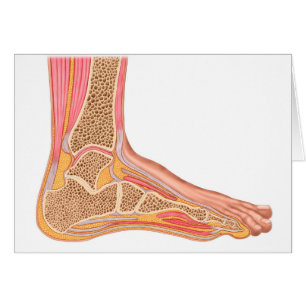

Section Longitudinale Du Pied Humain

Prix de vente 6,48 $CA. Prix Initial 7,20 $CA.